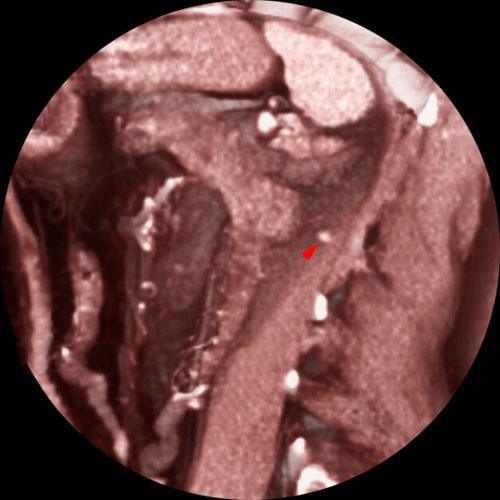

Recidiva local de hipernefroma

VR seccional. Visión sagital izquierda. TC contrastado en fase venosa, apreciándose una pequeña lesión nodular (punta de flecha), captante de contraste y pegada al músculo psoas, correspondiente a recidiva del hipernefroma